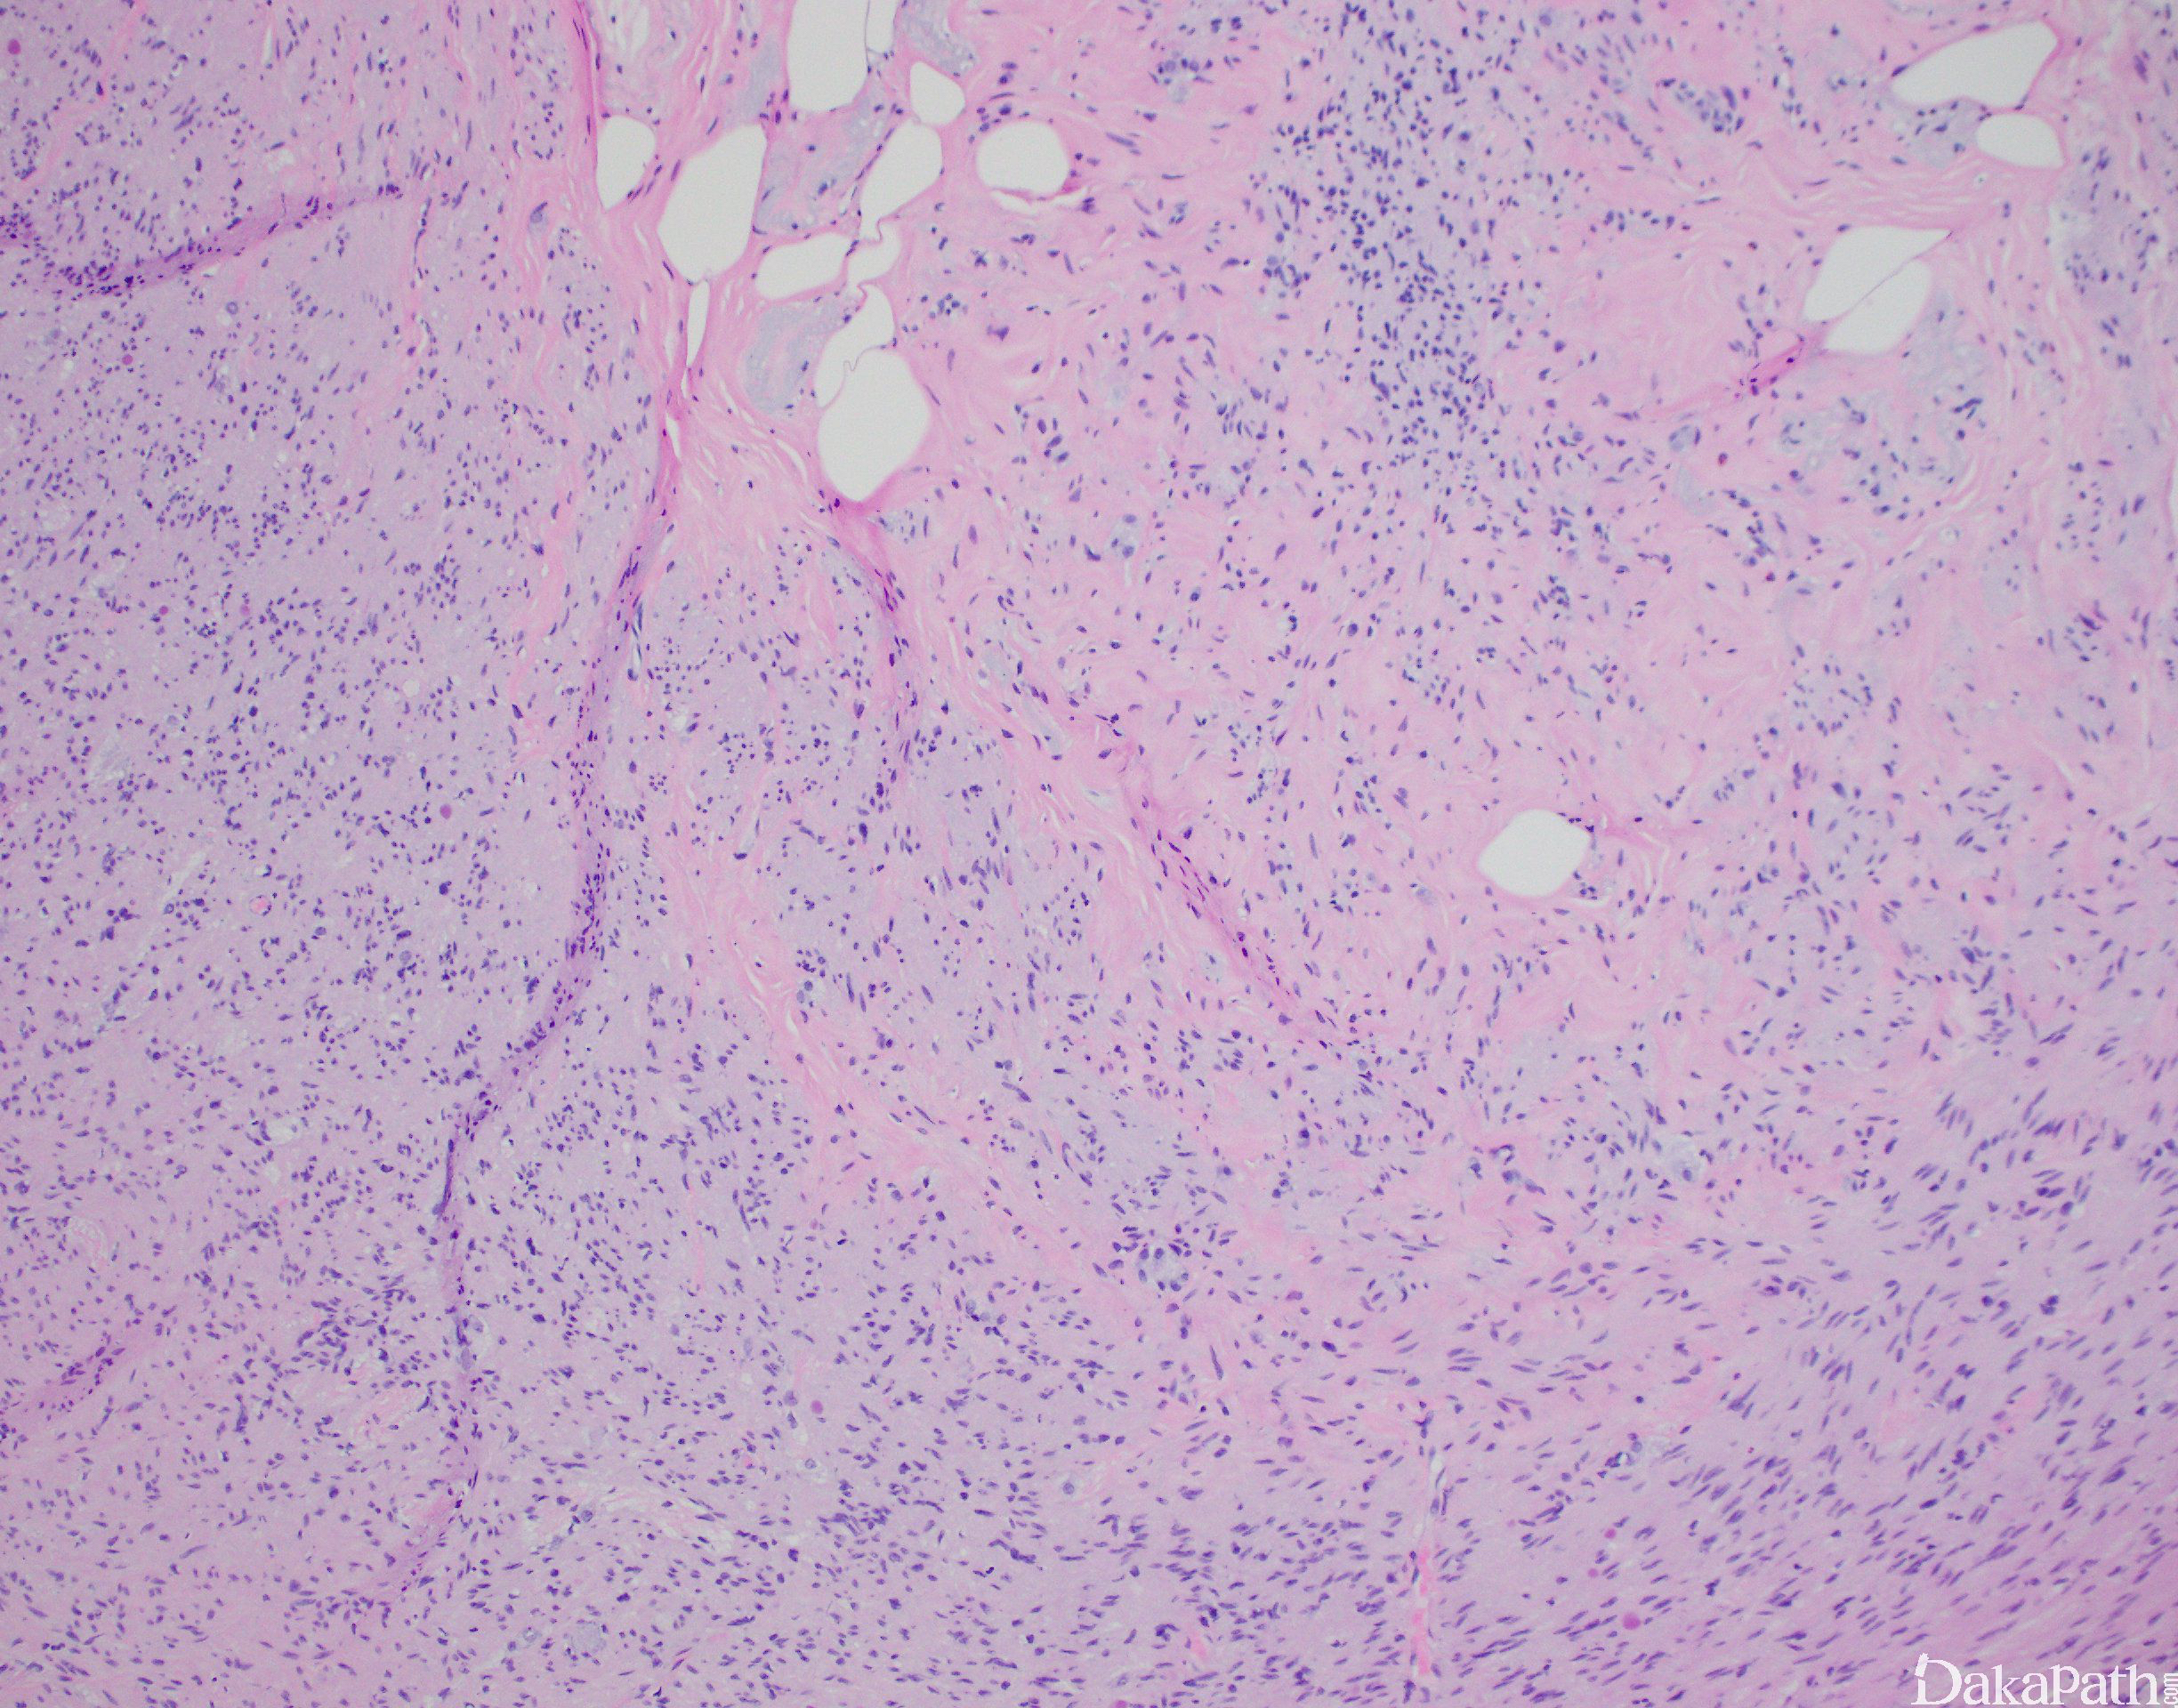

纤维化改变导致正常黏膜及淋巴结构的缺失,可闭塞阑尾腔。

组织上管腔被胶原组织取代,常伴黏液性背景。常见神经弥漫性增生及与纤维组织混合,可形成小神经瘤。纤维可能主要局限于黏膜,阑尾淋巴组织萎缩及消失,可见显著的肥大细胞。